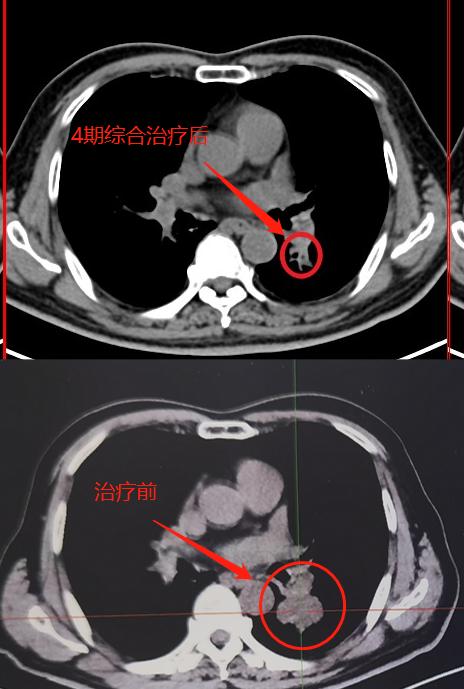

04. 患者采用免疫+化疗联合用药治疗:替雷利珠单抗+紫杉醇+卡铂 化疗4期。

05. 4期治疗后复查, 今日来复查 :病灶明显缩小,FDG-PET/CT肿瘤活性明显减低。

病灶由最大4cm,缩小1.5cm,最重要的是肿瘤活性明显减低,SUV最大值由10.2,降低到3.0,病灶内还有少许肿瘤活性残留。

病灶最大径约1.5m